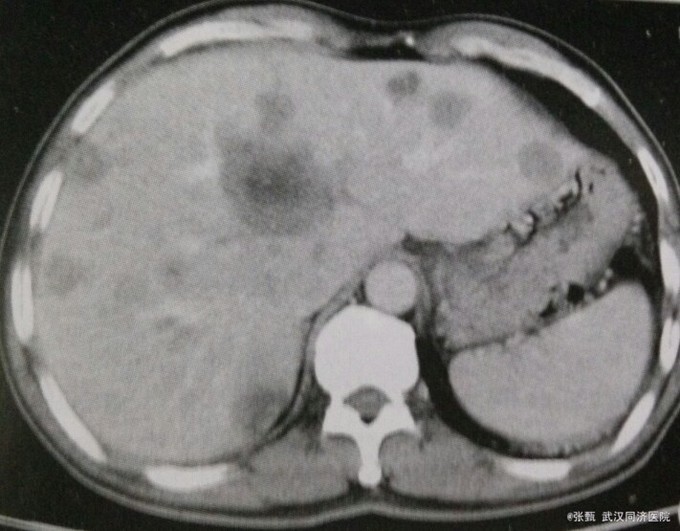

患者,男,60岁。 主诉:乙状结肠癌术后一年半,消瘦,纳差半年

查体:肝大,压痛 辅检:甲胎蛋白正常,CT示全肝广泛性不均匀低密度影,灶内见更低密度影,扫描动脉期肿瘤不规则强化,境界清楚,中央密度低,静脉期和实质期病灶强化消退呈现”牛眼征。“

诊断乙状结肠癌术后肝转移 建议行全身PET扫描,拒绝,行保守治疗

继发性肝癌占肝癌的相当大部分,大多为多发性结节,临床以原发癌表现为主,少数可仅有继发性肝癌的征象如肝肿大、肝结节、肝区痛、黄疸等。除个别来源于胃、结肠、胰的继发性肝癌病例外,血清AFP多呈阴性,CT显示为乏血供。根据AFP,原发癌病史及CT可诊断。